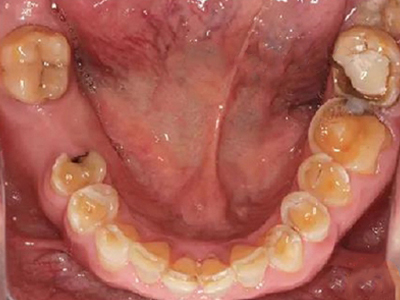

酸蚀症后排牙齿大量缺损图

酸蚀症患者的后排牙齿可发生大量缺损,一侧牙齿遗留圆盘状牙根,形似被切割,另一侧牙齿有大量凹陷坑洞,部分牙齿颜色发黑或呈黄褐色,其发生与长期接触酸性物质有关。